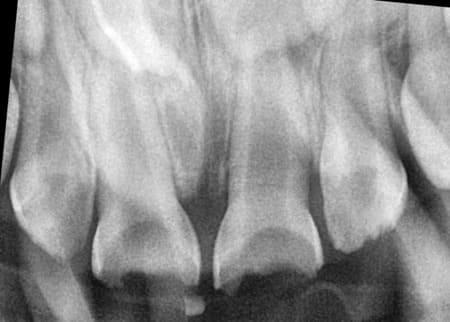

Детальніше...У Центрі Дитячої Стоматології лікаря Ковнацького ми віримо, що візит до стоматолога має бути для дитини не приводом для страху, а кроком до здорової та щасливої посмішки. Наша філософія базується на глибокому розумінні дитячої психології та фізіології, адже дитячі зуби потребують особливого підходу, а малюки – щирої турботи та довіри.